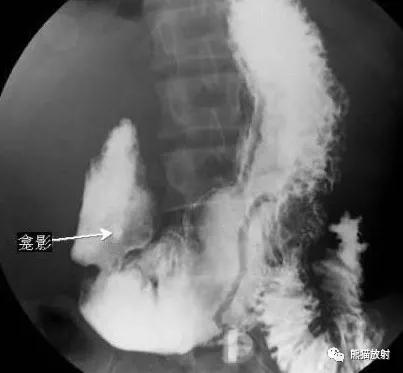

十二指肠反“3”字征(细箭头)及“垫征”(粗箭头)

胰头癌:胃肠造影示十二指肠扩大,内测缘出现压迹,呈“反3”征